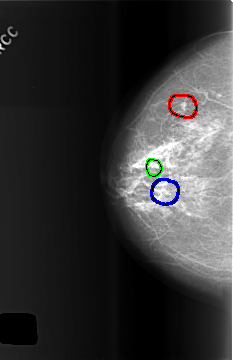

C_0508_1.RIGHT_CC

FILE: C_0508_1.RIGHT_CC.OVERLAY

TOTAL_ABNORMALITIES 3

ABNORMALITY 1

LESION_TYPE MASS SHAPE LOBULATED MARGINS CIRCUMSCRIBED

ASSESSMENT 2

SUBTLETY 5

PATHOLOGY BENIGN_WITHOUT_CALLBACK

TOTAL_OUTLINES 1

BOUNDARY

ABNORMALITY 2

LESION_TYPE CALCIFICATION TYPE PLEOMORPHIC DISTRIBUTION CLUSTERED

ASSESSMENT 3

PATHOLOGY BENIGN

ABNORMALITY 3

ASSESSMENT 4